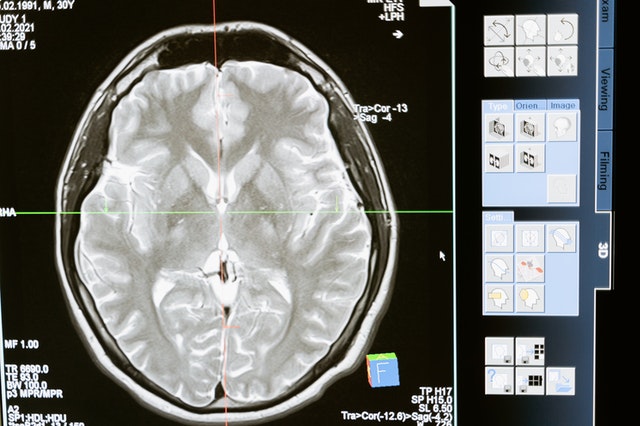

Los tumores cerebrales malignos han sido siempre un reto para la neurocirugía, dado que muchos de estos tumores presentan ramificaciones que se extienden más allá de los límites visibles en las resonancias cerebrales o incluso por el cirujano durante el procedimiento quirúrgico. El objetivo siempre es resecar la totalidad del tumor, pero conservando las áreas funcionales del cerebro (lenguaje, memoria, sensibilidad, visión, etc.) que permitan una óptima calidad de vida. Tras la cirugía de muchos de estos tumores, es importante el seguimiento por un especialista donde que existe la posibilidad de reaparición del tumor, con la necesidad consecuente necesidad de nuevos tratamientos.

Un importante artículo en la revista Nature descubrió recientemente el comportamiento de algunos de estos tumores cerebrales y cómo muchas veces reaparecen lejos de la zona inicial intervenida. Sin embargo, esta zona está frecuentemente relacionada en función (visión, lenguaje, etc.) con la anterior. Es decir, muchos tumores cerebrales se propagan (utilizando las neuronas sanas) por zonas cerebrales con funciones relacionadas. Conocimientos como este ayudarán en un futuro inmediato a los especialistas a poder predecir con un margen de error las posibles zonas de reaparición de estos tumores para tratarlas de forma temprana.